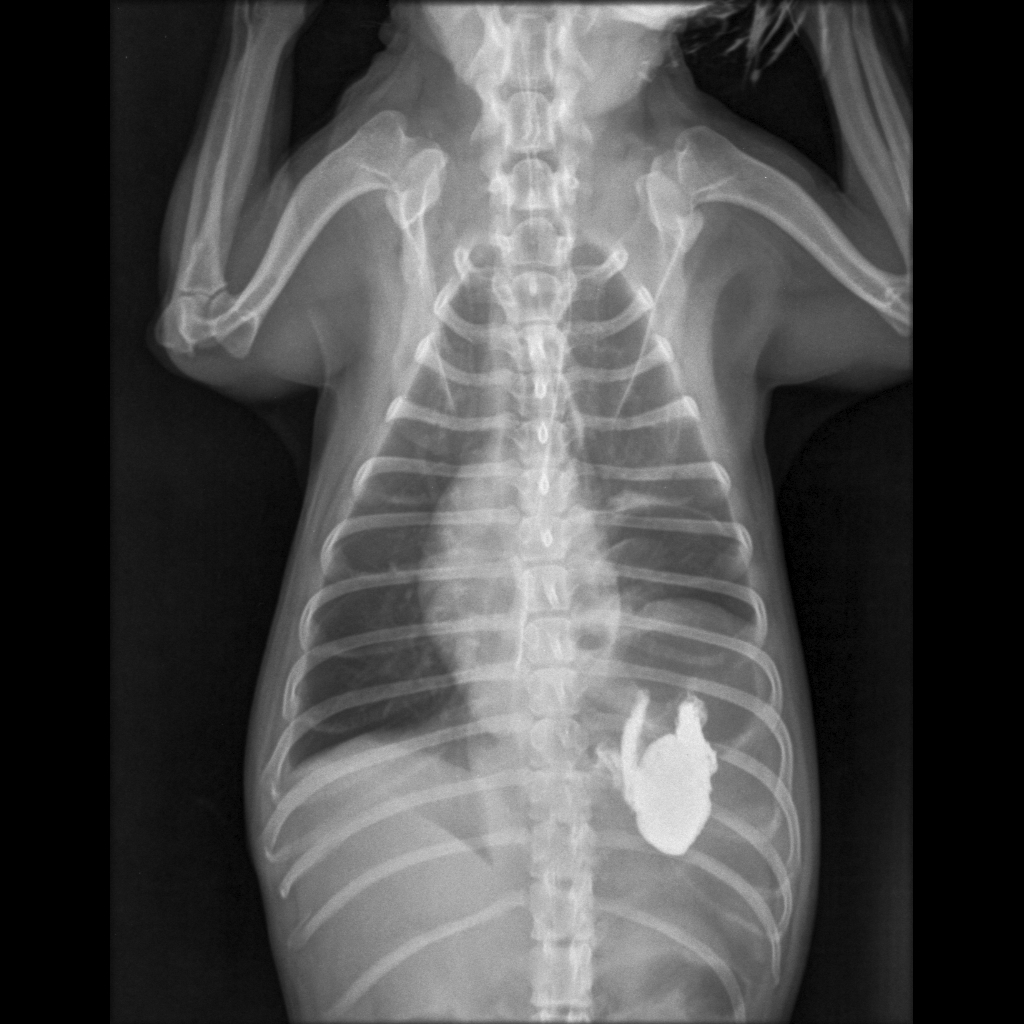

Radiodiagnóstico Veterinário Yorkshire, 05 anos.

Radiodiagnóstico Veterinário Anatomia radiográfica do tórax